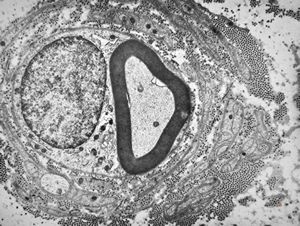

![F,23y. | n.suralis - hypertrophic demyelinating neuropathy [onion bulb] F,23y. | n.suralis - hypertrophic demyelinating neuropathy [onion bulb]](../img/OGDEM/015 Soft tissues/0076.jpg)

F,23y. | n.suralis - hypertrophic demyelinating neuropathy [onion bulb]